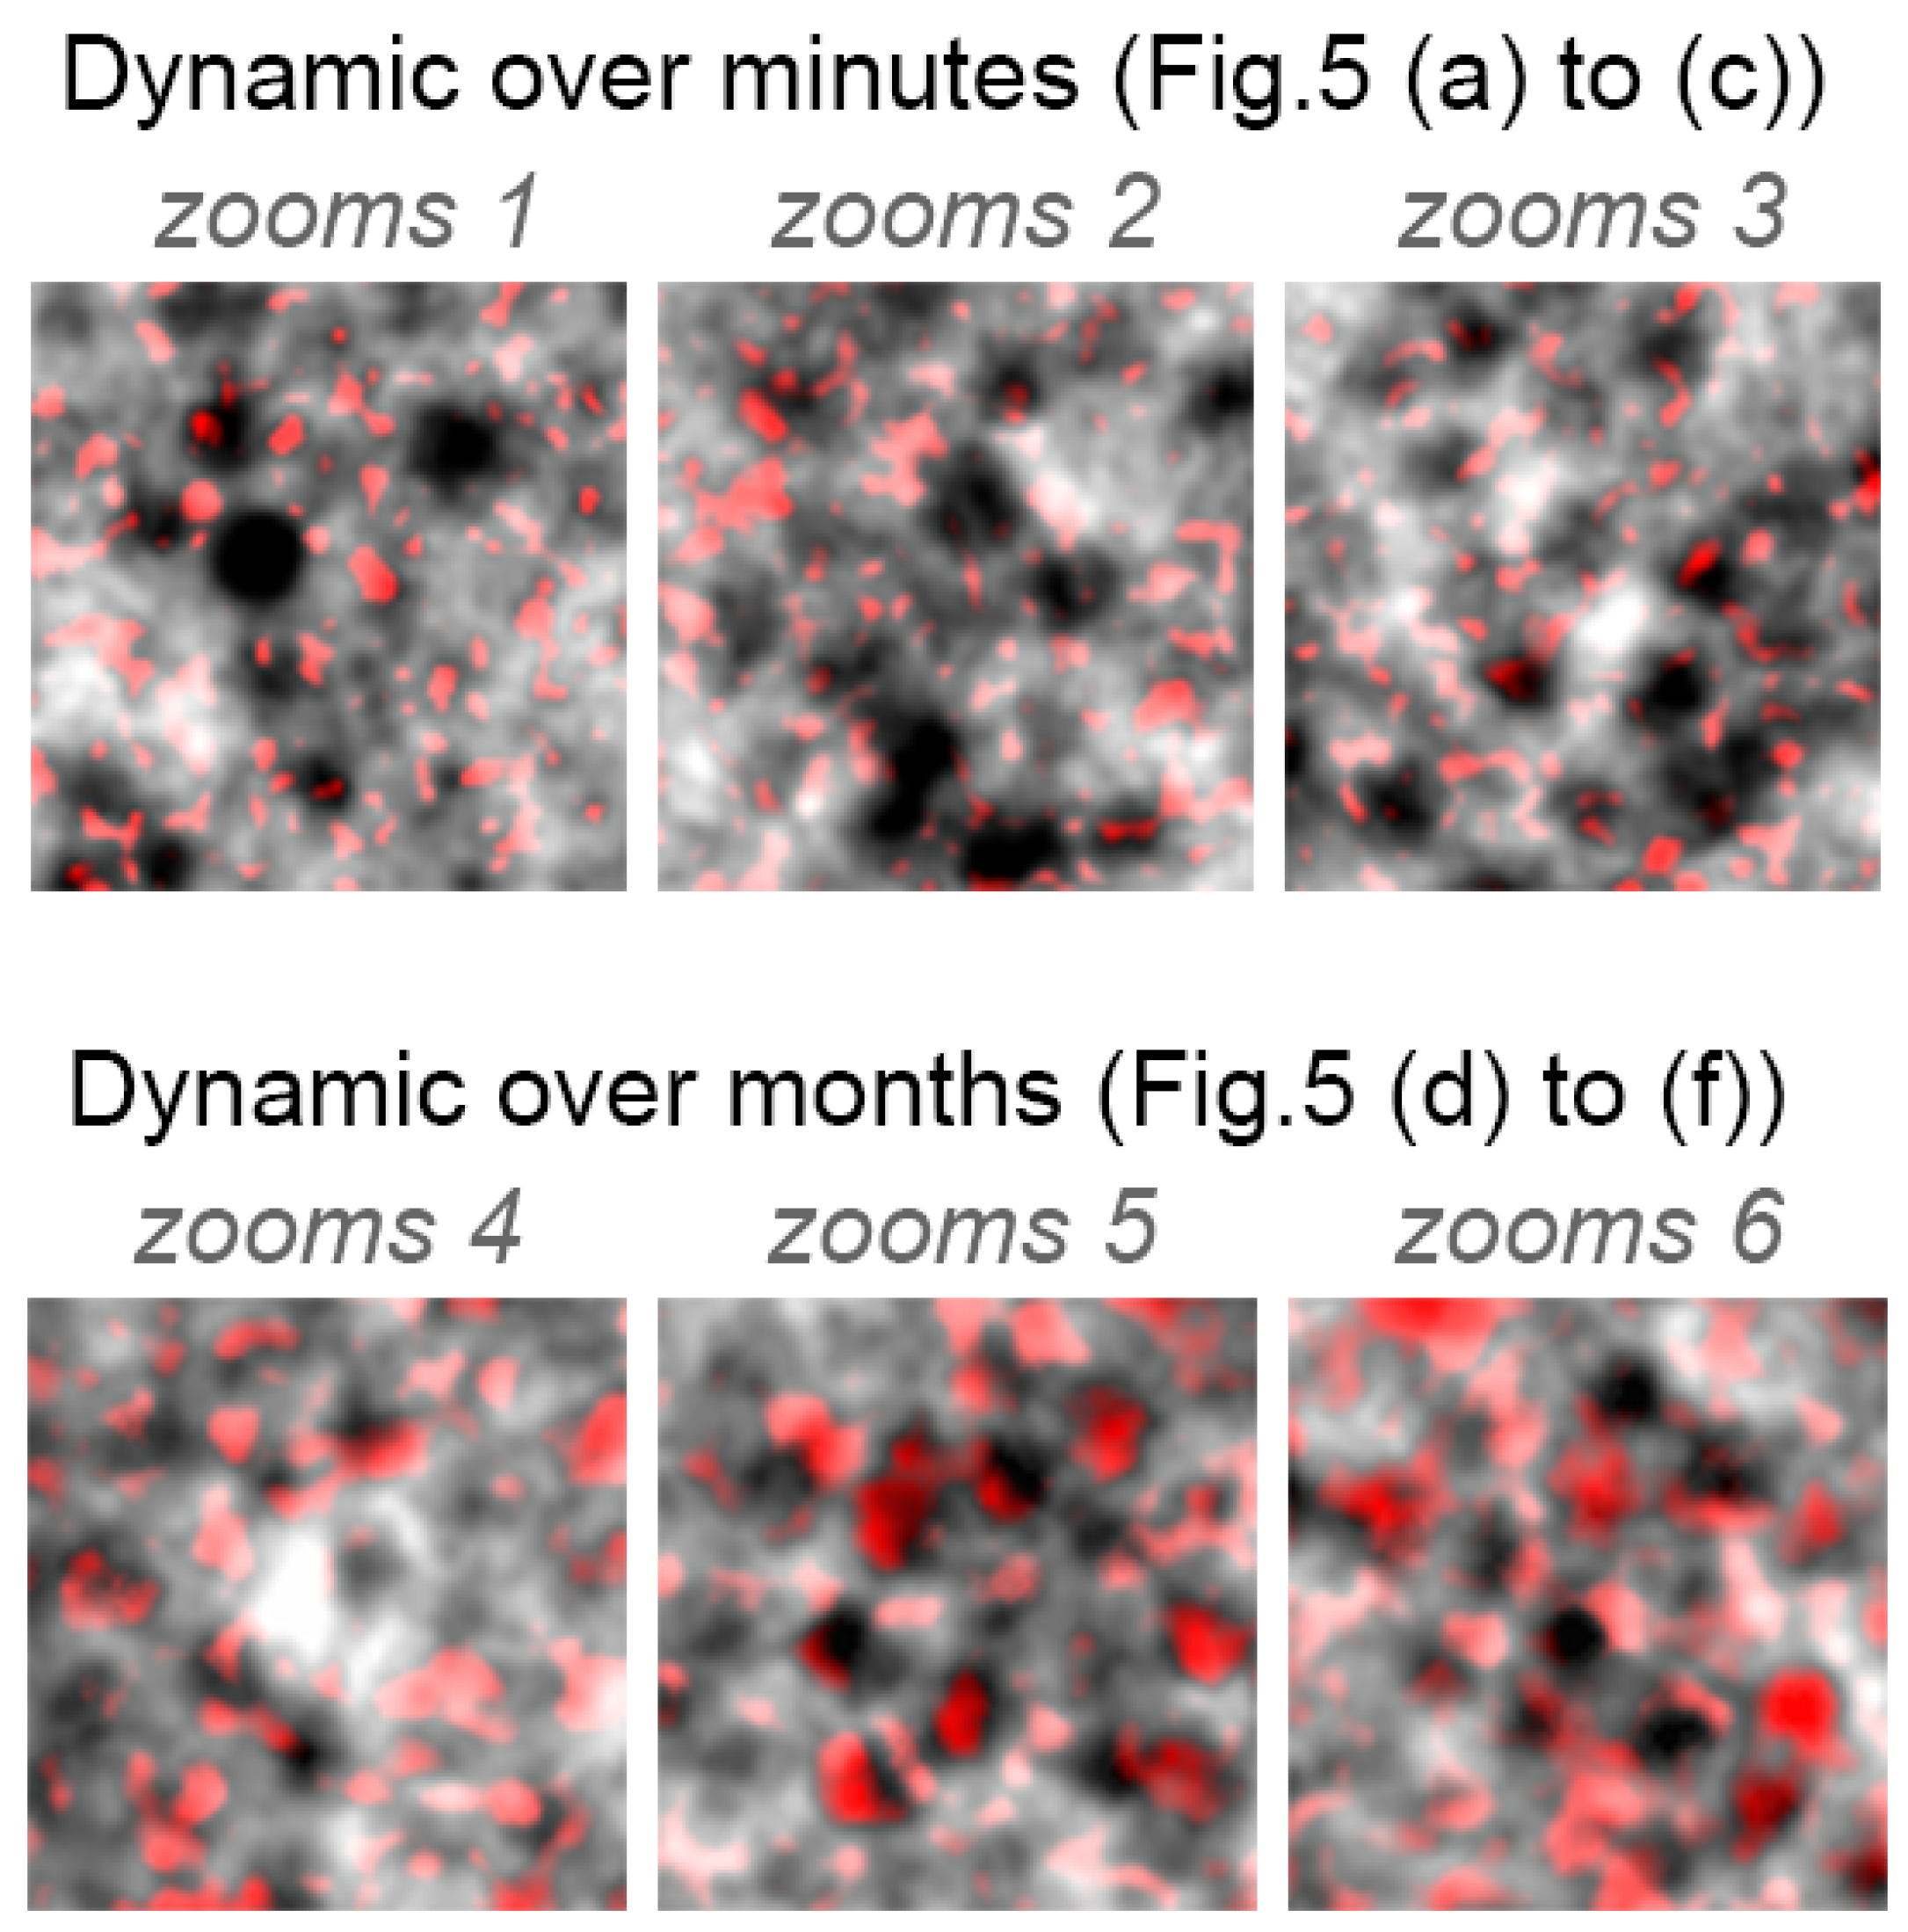

3.2. RPE Mosaic Variations with Time in Healthy Retina

Appendix B. Colored Standard Deviations for Zooms 1–6 (from Figure 5)